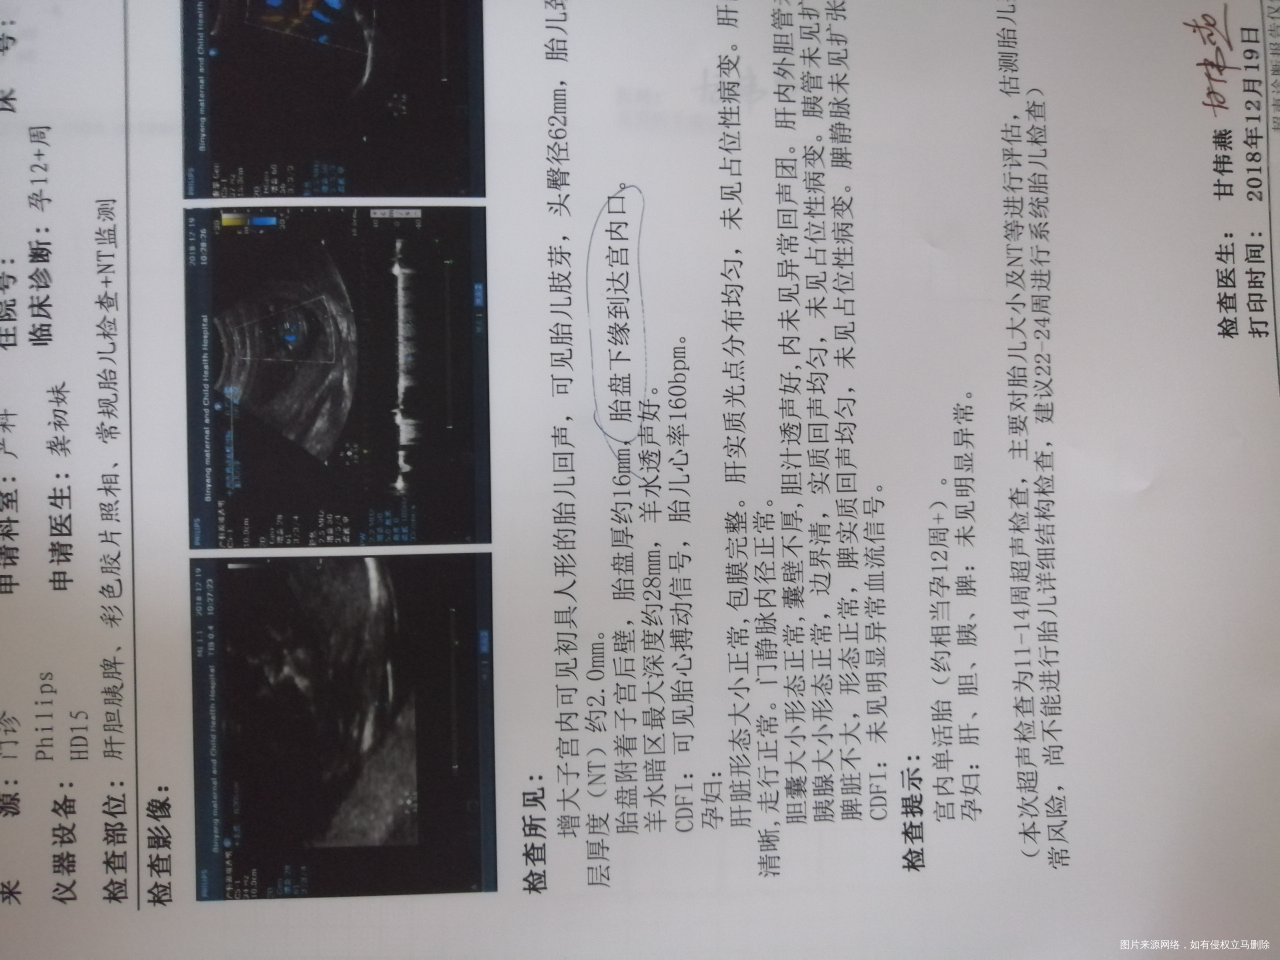

补充说明,宝妈。1 正常胎盘下缘距宫颈内口大于3cm为佳。目前已经达宫颈内口,这是有流产风险的。与你的不舒服也有关系的。 2 近期注意不要负重劳累,夫妻不要同房,保持大便通畅,静卧观察。必要时用中成药固肾安胎或是保胎无忧之类的保胎。还有可以休息时适当抬高臀部。这个需要动态观察,可能之后随着宝宝发育子宫增大胎盘随着长上去。大概5--6个月之后会长上去,但是一定动态观察,如果腹痛或是流血等不适加重,一定及时宫颈环扎保胎。按照你的情况而定,医生的建议为准。3 定期产检,祝你好孕。如果我的建议对您有帮助,请记得选择点击采纳

刘超

你好,孕12周,可以nt排畸检查,同时观察到胎盘下缘距离宫颈口比较近,为胎盘低置,随着妊娠月份增加,会逐渐往上生长的,需要定期复查。胎盘低置状态比较常见,不要剧烈活动及久坐久站,尽量卧床休息,禁止性生活刺激,增加休息时间,一般没有腹痛出血的情况,暂时观察就可以。怀孕28周胎盘下缘覆盖宫颈内口才能诊断前置胎盘,根据你提供的信息,你现在怀孕12周,随着孕周增大,胎盘自己会慢慢长上去一点,但是完全长上去不可能,有可能是边缘性前置胎盘,今后加强产检,饮食以清淡为主,多吃高维生素高蛋白的食物,不能吃辛辣刺激性的食物,有利于胎儿的生长发育,多吃蔬菜水果,保持大便通畅,用高点的坐便器,放松心情,你的心情对胎儿的生长发育有很大的影响的,没事的,放心吧,祝好孕!觉着我的回复对您有帮助,记着帮忙点击采纳,谢谢!